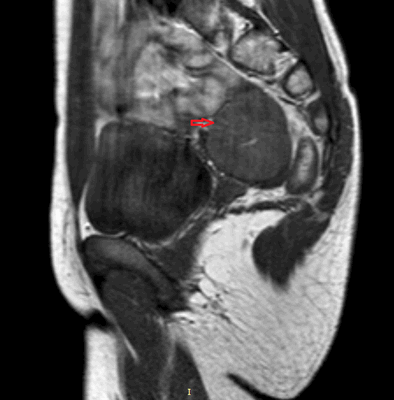

Рисунок 2. - семинома яичка: а — макропрепарат, б — МРТ.

- КТ (расшифровка: компьютерная томография), МРТ (расшифровка: магнитно-резонансная томография), ПЭТ-КТ (расшифровка: позитронно-эмиссионная томография, совмещенная с КТ). Эти обследования необходимы, чтобы рассмотреть структуры организма послойно и визуализировать опухоль. Они показывают, как сильно распространен патологический опухолевый процесс на находящиеся рядом ткани и органы, есть ли поражение костей. КТ - это самый чувствительный метод для обнаружения метастазов в легких. Проведение МРТ и КТ головного мозга необходимо, чтобы обнаружить и визуализировать герминогенные новообразования эпифиза.

Диагноз устанавливается с учетом жалоб, анамнеза, результатов внешнего осмотра, лабораторных и инструментальных исследований. Пациентов с подозрением на семиному направляют на УЗИ органов мошонки. Для выявления метастазов назначают рентгенографию грудной клетки, КТ брюшной полости, МРТ печени, сцинтиграфию костей скелета и другие исследования. В процессе дифференциальной диагностики семином и других злокачественных новообразований яичка используют анализы крови на онкомаркеры.